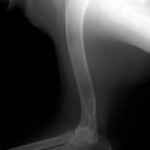

若齢動物において、橈骨と尺骨は互いに同調した成長をしています。一方の骨の成長に障害が生じると、他方の骨に変形や彎曲、関節形態の異常が引き起こされます。これらの変形が動物自身の補正可能範囲を超えてしまうと、深刻な機能異常を呈し、歩様は著しく変化します。

レントゲン所見として、橈骨の前屈、短縮、外反変形、指端の外旋、肘関節の亜脱臼が程度により認められます。

横断骨切り術、開放性楔形骨切り術、閉鎖性楔形骨切り術、斜め骨切り術などが報告されています。

■ミニチュアダックスフント 1歳 去勢オス

前肢の成長板早期閉鎖、前肢の重度の外反変形が認められました。

関節面の変形が重度に認められます。